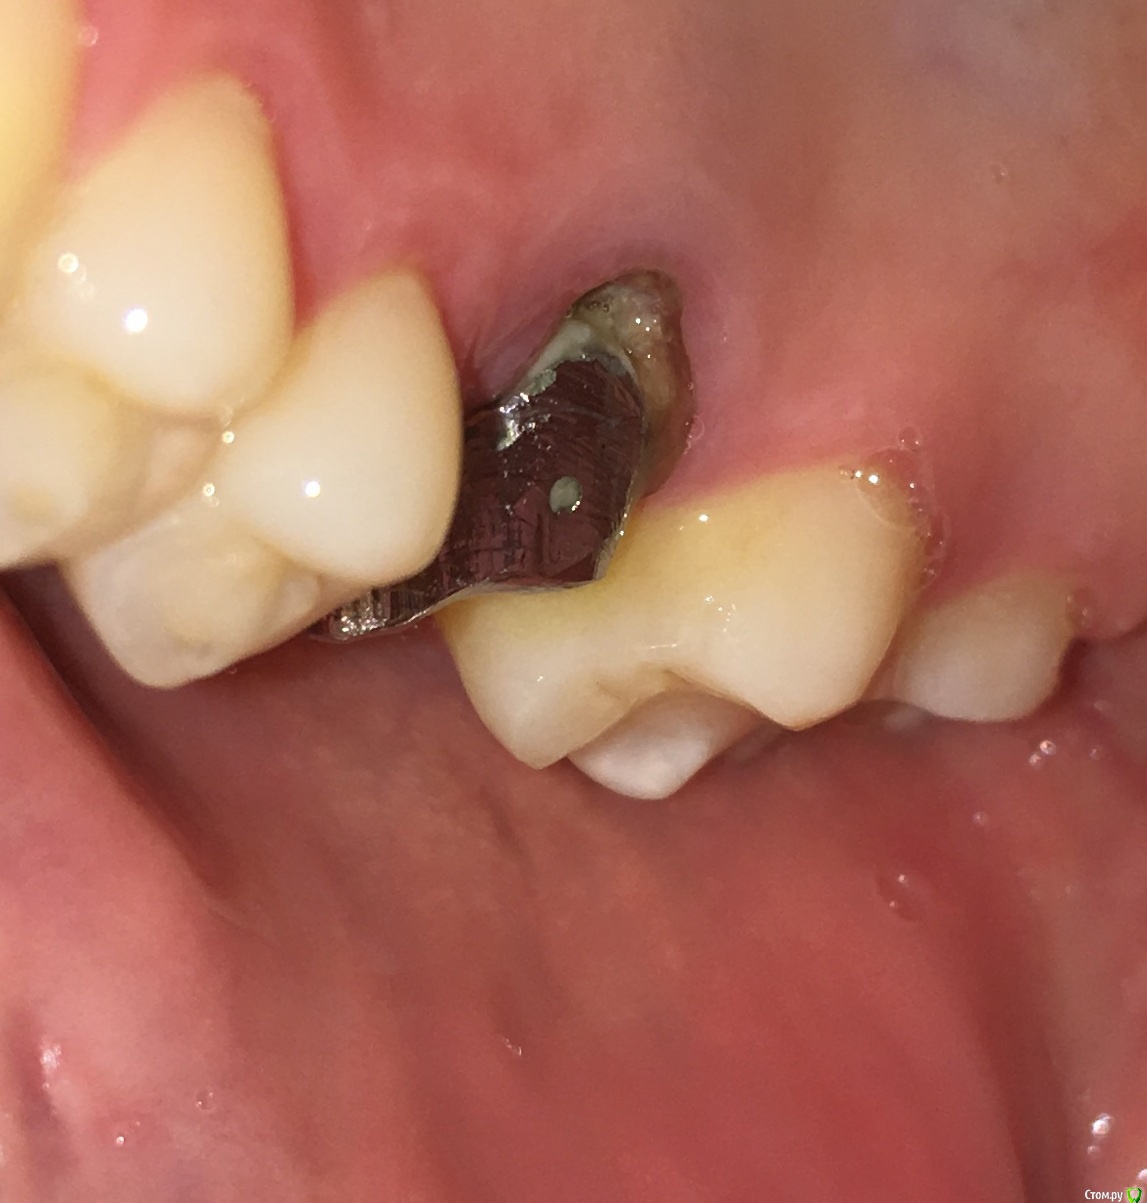

MichaelV Опубликовано 17 октября, 2019 Автор Поделиться Опубликовано 17 октября, 2019 (изменено) Вот какая ситуация на сегодня.Забыл сказать, что в прошлый прием (неделю назад, когда я написал этот пост), мне немного подточили опорный зуб (возможно и часть вкладки, но не уверен) около десны. Изменено 17 октября, 2019 пользователем MichaelV Ссылка на комментарий

chervoncevdaniil Опубликовано 17 октября, 2019 Поделиться Опубликовано 17 октября, 2019 Чуда не произошло 1 Ссылка на комментарий